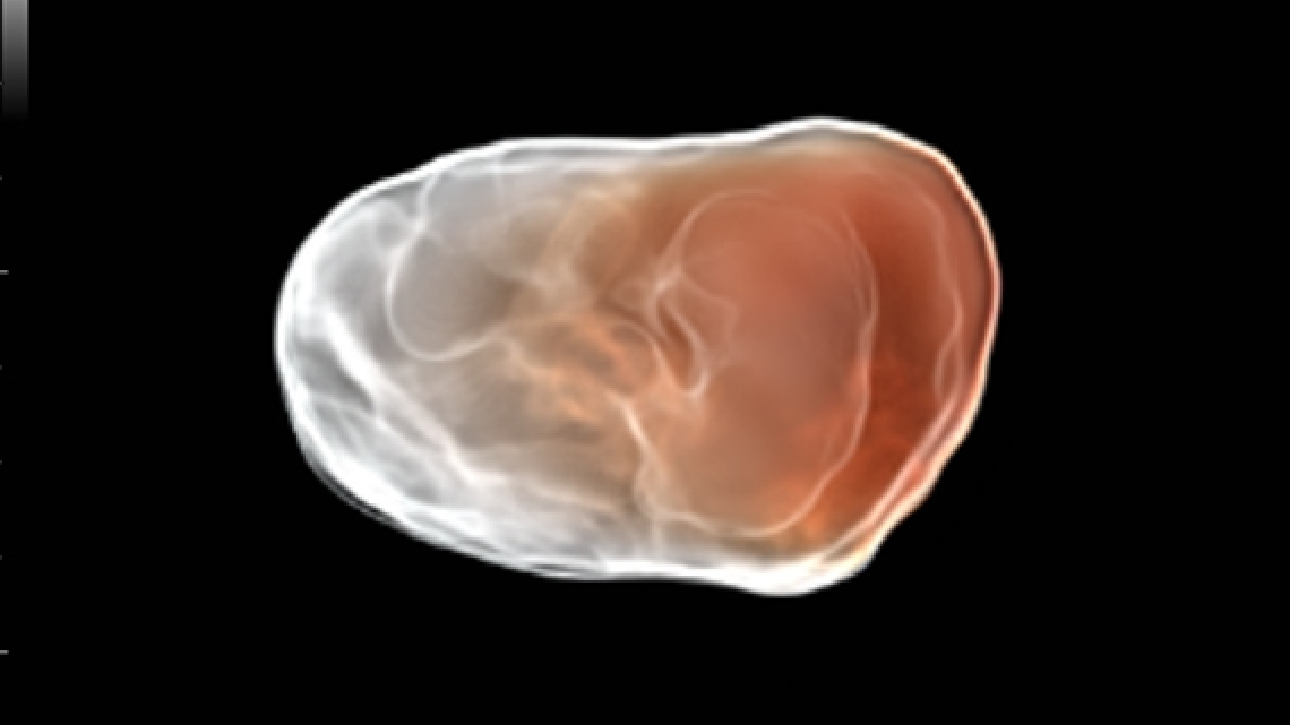

ImĂĄgenes clĂnicas